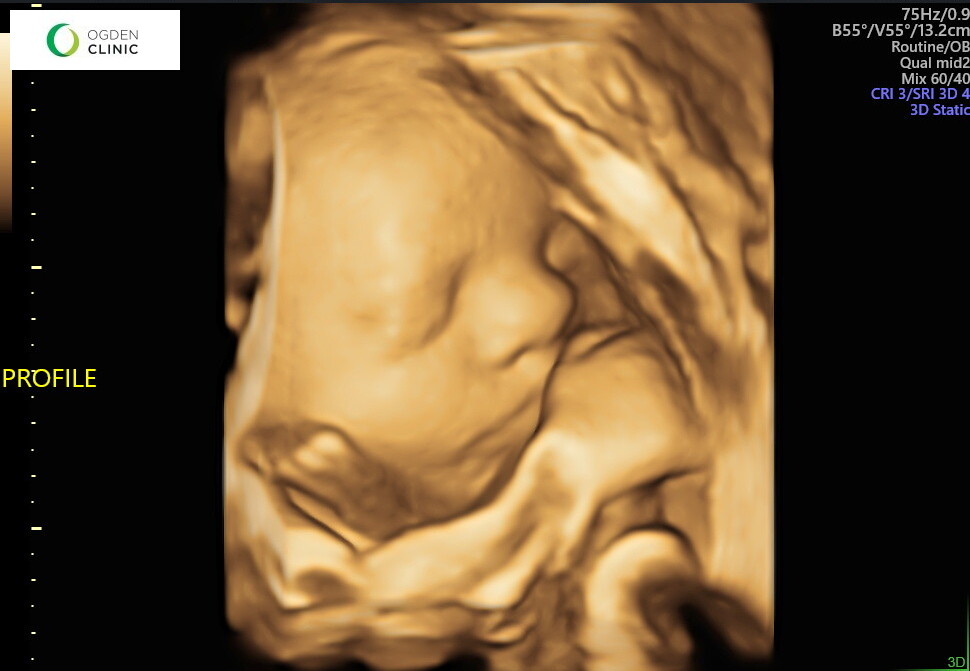

Baby bro is looking so cute! We loved getting some ultrasounds of him this month and seeing his cute face up close. He’s a mover, always has his hands covering his face in ultrasounds, and we are so excited he’s coming so soon!